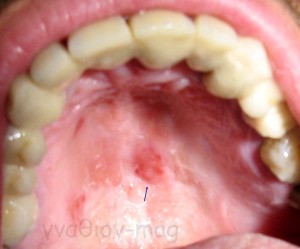

Ωστόσο, σαν γενική αρχή, αν μια βλάβη παραμένει στο στόμα περισσότερο από μία εβδομάδα χωρίς σημεία ύφεσης, ακόμη κι αν είναι ανώδυνη, θα πρέπει να εξετάζεται από ειδικό γιατρό (Εικόνα 2).

Οι πιο συχνές βλάβες στο στόμα είναι τα αποστήματα, τα οποία όταν οφείλονται σε μικροβιακές λοιμώξεις δοντιών της άνω γνάθου μπορούν να εκδηλώνονται και στην υπερώα (Εικόνα 3). Η θεραπεία τους προϋποθέτει την θεραπεία του υπεύθυνου δοντιού.